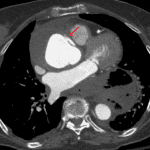

Sample ReportType A aortic dissection extending from the aortic root to the distal arch with associated small hemopericardium and aneurysmal dilation of the ascending aorta measuring up to 7 cm in diameter. The false lumen is largely thrombosed with extensive intramural hematoma extending into the origins of the brachiocephalic and left common carotid arteries, which remain widely patent. Recommend surgical evaluation.